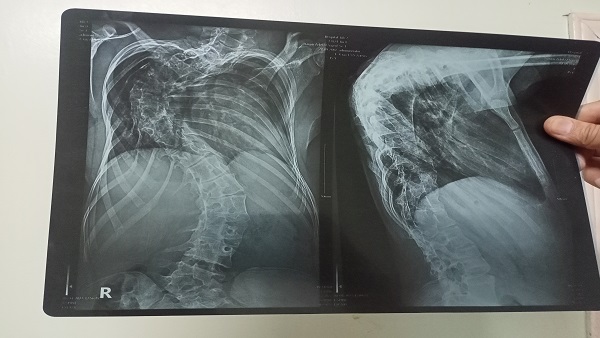

قصة تفوق عظيمة جدا لطالبة اسمها حنين عادل السيد، ابنة قرية شبرا زنجى إحدى قرى مركز الباجور التابع لمحافظة المنوفية، ولدت بمرض فى العمود الفقرى عبارة عن نقص فقرات الأمر الذى أصبح يمنعها من الحركة إلا قليلًا بسبب حدوث تقوس فى العمود الفقرى.

تسبب ذلك المرض فى التزام حنين النوم فترات طويلة كما استلزم عدم الحركة إلا عند الضرورة فقط، لكنها لم تستسلم وقررت التفوق وتمكنت من الحصول على الدرجة الكاملة فى امتحانات الشهادة الإعدادية فى إمتحانات يناير وحصلت على المركز الأول على مستوى المحافظة.

لم تتمكن حنين من الحصول على الدرجة الكاملة فى امتحانات نهاية العام بسبب إجرائها لعمليات جراحية فى العمود الفقرى وحصلت على 278 درجة من 280 حيث فقدت درجتين فقط فى مادة اللغة العربية.

لم تكن الثلاث عمليات التى أجرتهم حنين هي أول الجراحات التى خضعت لها لكنها أجرت قبل ذلك 10 جراحات فى العمود الفقرى منذ ولادتها حتى أخبر الأطباء أسرتها بأنهم فعلوا ما فى إستطاعتهم ولم يعد هناك ما يستطيعون فعله، وأن الأمر بات يتطلب السفر لإجراء عملية جراحية بدولة ألمانيا.